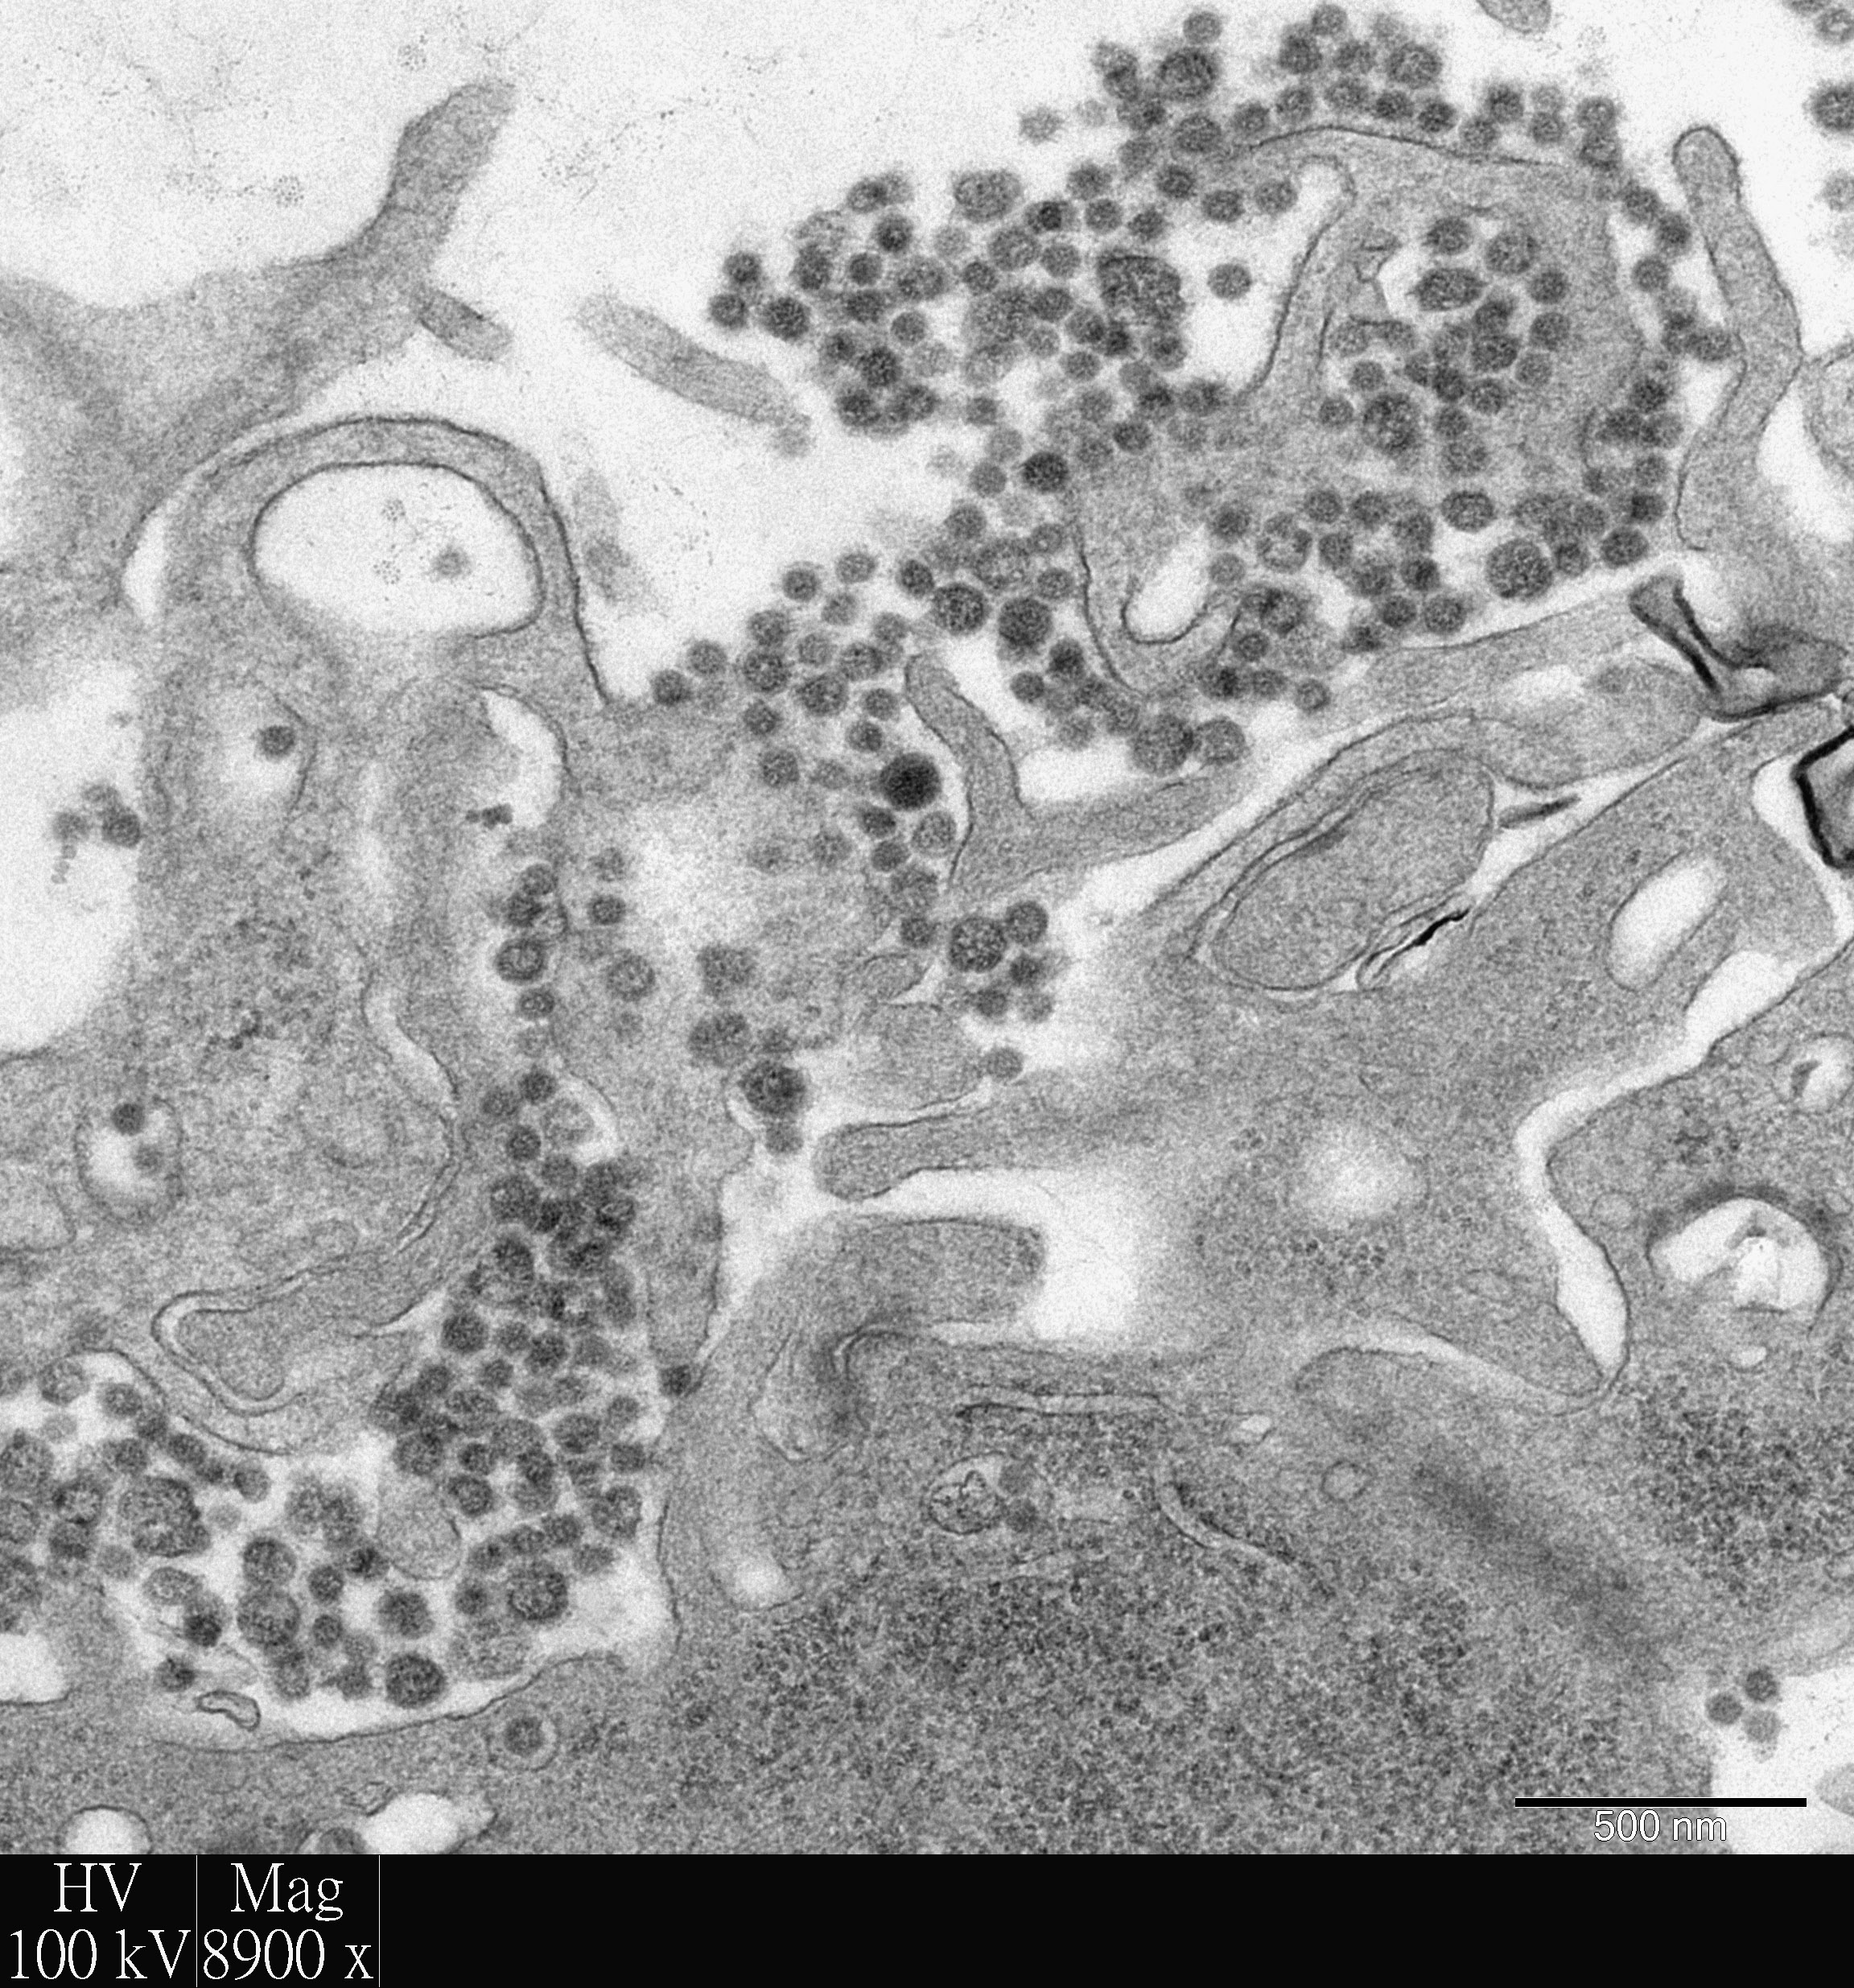

香港大學李嘉誠醫學院的研究人員利用其世界頂尖的「人類呼吸道外植體培養技術」研究新興呼吸道病毒,並在最新出版的刊物中發表可用於改善治療中東呼吸綜合症 (MERS) 的研究成果。研究證明結合使用目前已獲得臨床使用許可的干擾素和環孢黴素,較使用單一藥物治療或零治療更能顯著抑制中東呼吸綜合症冠狀病毒在人類支氣管和肺部中複製及造成組織損傷。研究結果已於抗病毒治療領域的權威期刊《抗病毒研究》(Anti-viral Research)發表。(按此瀏覽期刊文章)

由於過往利用細胞培養技術或實驗動物不能完全真實地呈現人類感染嚴重呼吸道病毒時的情況,香港大學病理學系黎國思教授以及公共衞生學院的陳志偉博士、陳韻怡博士、潘烈文教授及裴偉士教授於二零零五年共同研發「人類呼吸道外植體培養系統」,旨在為尋找以實驗室為本的方法研究嚴重呼吸道病毒感染,同時亦能更真實地反映疾病的機制及用於治療人類時的成效。

外植體培養系統在獲得道德許可的情況下,利用瑪麗醫院丟棄的呼吸道組織作研究。經過八個多月的優化後,系統獲世界衛生組織列為研究動物流感病毒感染大流行風險評估的模型,同時亦被生物技術公司用於評估潛在的抗病毒化合物。食物及衛生局以及大學教育資助委員會研究資助局提供的資金亦使該系統得以開發、優化和維持。